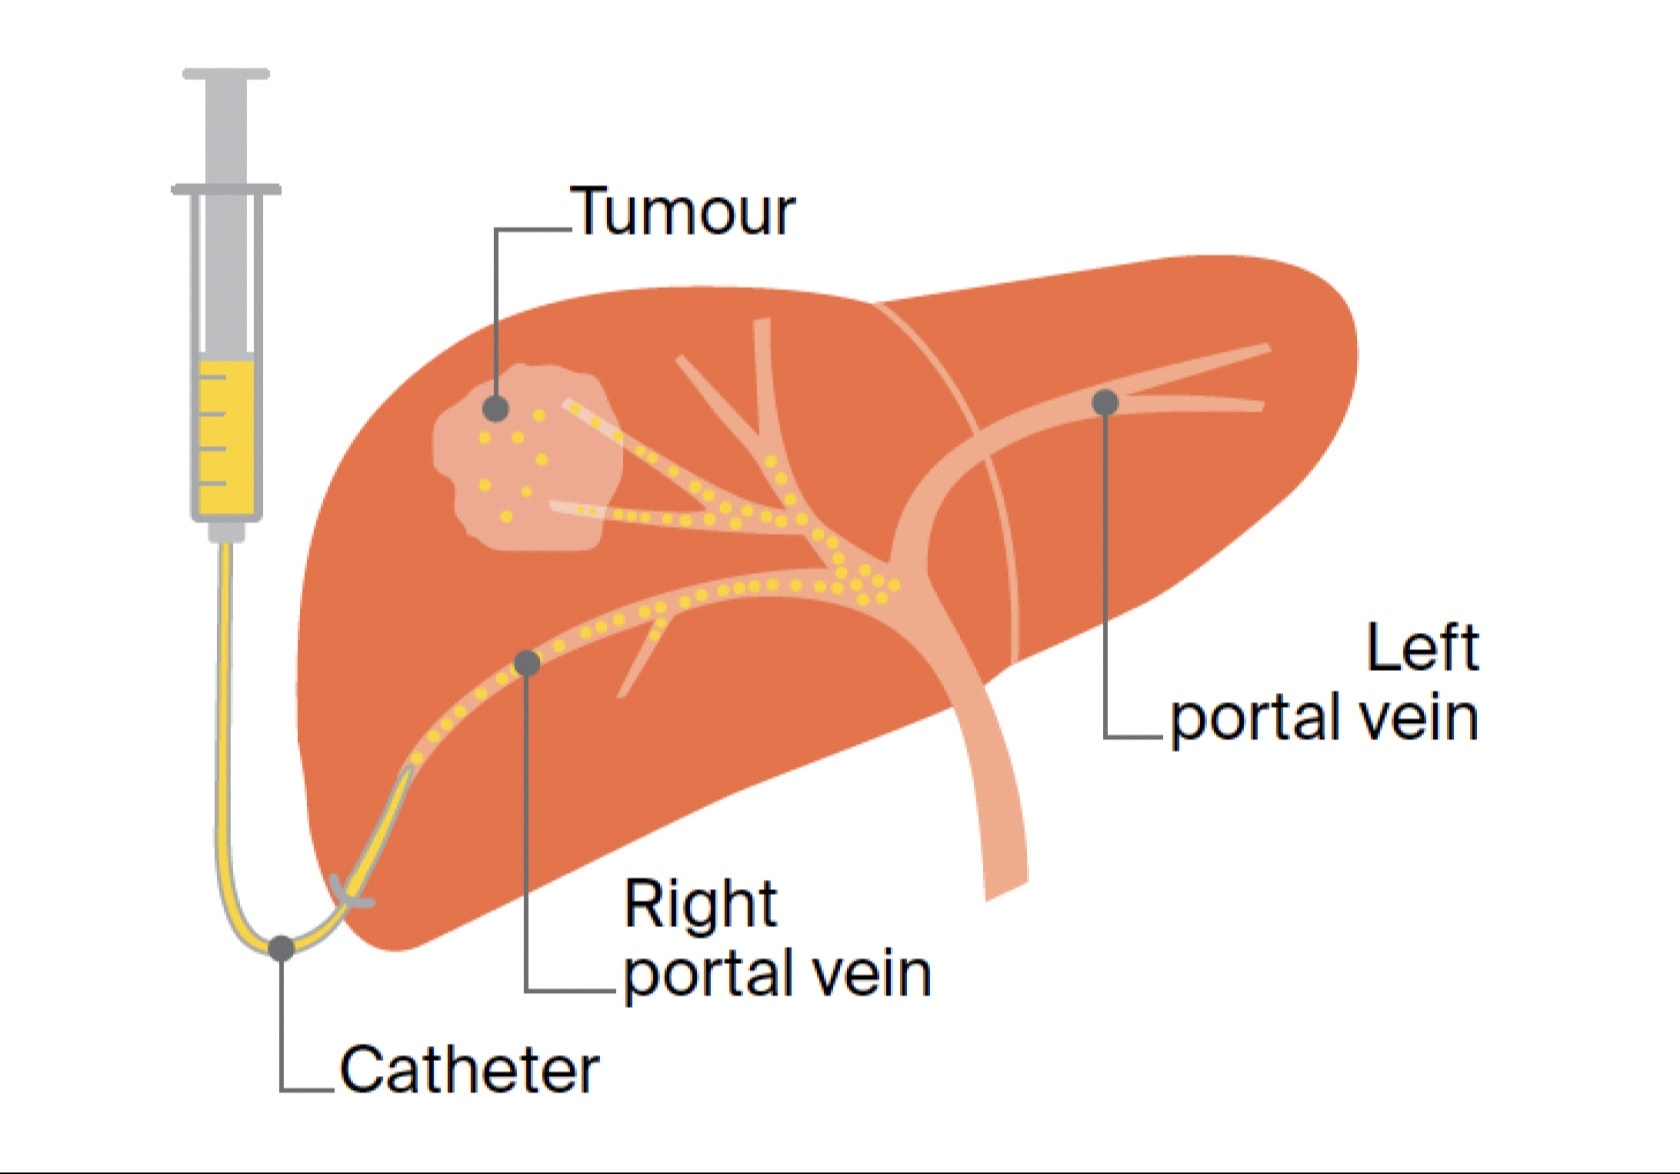

Is University Hospital Frankfurt suitable for patients with cancer?

It is one of the largest institutions dealing with cancer treatment. The oncology unit has a spiral tomograph, a gamma knife, PET, and other latest-generation equipment. Moreover, the team has performed hundreds of successful operations to treat the most complex oncological diseases.